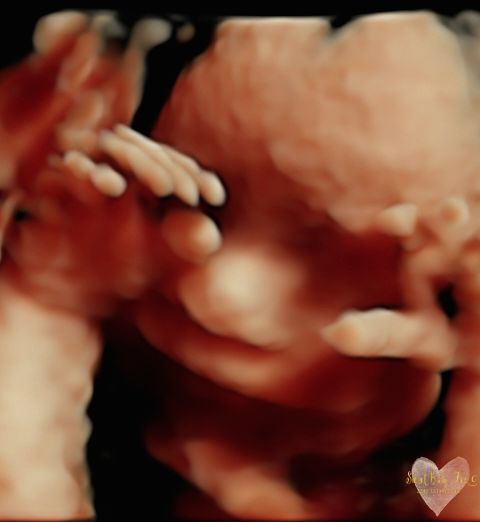

3D/4D/5D Ultrasound Gallery

Take a peek at our Photo Gallery. All of our 2D, 3D, 4D, HD elective ultrasound images are truly ours. They come directly off our machine from our highly trained staff. We can start getting great 3D/4D images as early as 10 weeks!